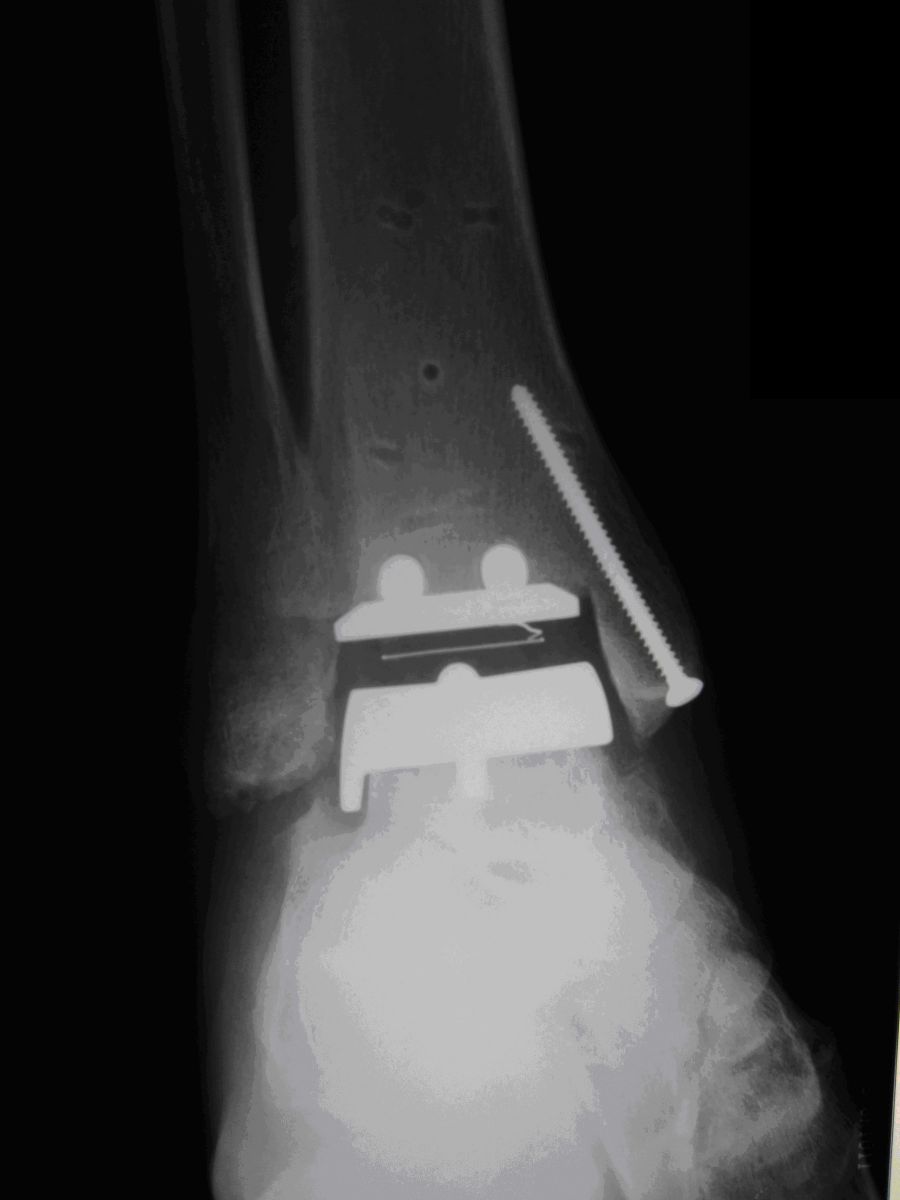

Αρθροπλαστική ποδοκνημικής

Πρόκειται για αντικατάσταση της φυσικής άρθρωσης με τεχνητή (μέταλλο και πλαστικό’). Η αρθροπλαστική έχει σκοπό να διατηρήσει κίνηση στην άρθρωση (τεχνητή πλέον). Αρθροπλαστικές ποδοκνημικής γίνονται από το 1970, όμως τα αρχικά αποτελέσματα ήταν απογοητευτικά. Τα εμφυτεύματα που χρησιμοποιούνται σήμερα έχουν γενικά βελτιωθεί, όπως και η γνώση και χειρουργική τεχνική, ιδιαίτερα σήμερα που υπάρχουν ορθοπαιδικοί χειρουργοί εξειδικευμένοι στις παθήσεις του ποδιού. Σε σχέση με τις αρθροπλαστικές γόνατος και ισχίου (που είναι οι πιο συχνές), οι αρθροπλαστικές ποδοκνημικής υστερούν τόσο σε ότι αφορά τις ενδείξεις (σε ποιον ασθενή πρέπει να γίνονται) όσο και στη ‘διάρκεια ζωής’ τους. Έχει ένδειξη για τελικού σταδίου αρθρίτιδα (όπως και η αρθρόδεση), όταν όλα τα άλλα μέτρα αποτυγχάνουν να ελέγξουν τον πόνο. Ιδιαίτερα ενδείκνυται σε ασθενείς που έχουν αρθρίτιδα και σε άλλες αρθρώσεις του ποδιού που απαιτούν αρθρόδεση. Η αρθροπλαστική μπορεί να διατηρήσει κάποιο εύρος κίνησης.

Η επέμβαση γίνεται με γενική ή ραχιαία αναισθησία. Γίνεται μια χειρουργική τομή 15 εκατοστών περίπου στην πρόσθια επιφάνεια της άρθρωσης. Τοποθετούνται εμφυτεύματα: μέταλλο στην κνήμη και τον αστράγαλο και ανάμεσά τους κινούμενο πολυαιθυλένιο (πλαστικό). Μετά το χειρουργείο χρησιμοποιείται γύψος για 3 εβδομάδες με ελάχιστη φόρτιση και κατόπιν αφαιρούμενος κηδεμόνας (μπότα) για άλλες 3 εβδομάδες επιτρέποντας τη φόρτιση.